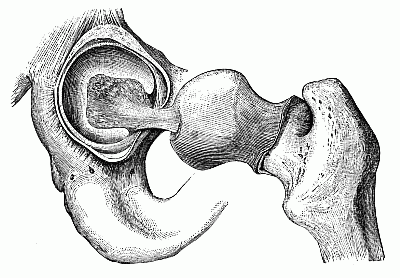

The hip-joint.

The hip-joint.

This kind of joint is the round end or ball of a long bone, which moves in a hole, called a socket.

Your joints do not creak or get out of order, as those of doors and gates sometimes do. A soft, smooth fluid, much like the white of an egg, keeps them moist and makes them work easily.[12]